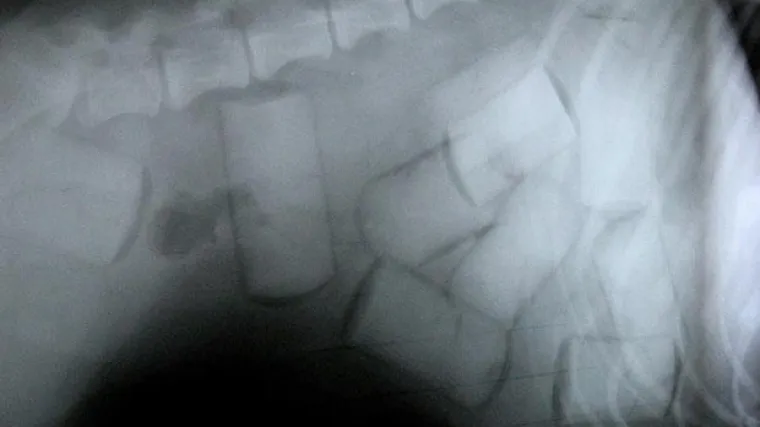

Talijan umro sa 103 kapsule kokaina u želucu

Talijanski državljanin umro je u preuanskom gradu Cuscu pošto je progutao 103 kapsule kokaina, objavila je službena peruanska agencija Andina citirajući policijske izvore.

44-godišnji Roberto Palazzotti hospitaliziran je u četvrtak u Cuscu zbog jakih želučanih bolova te umro tri dana poslije od srčanog udara. Na autopsiji je otkriveno da je u organizmu nosio 407 grama kokaina raspoređenih u 103 kapsule.